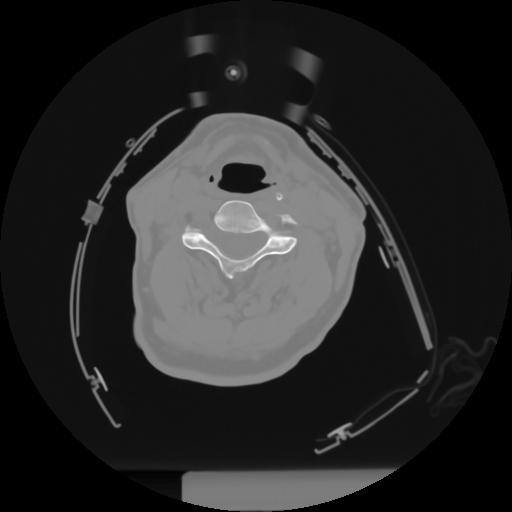

10 P.BLANDAS,,Axial,2.0,P.BLANDAS,,